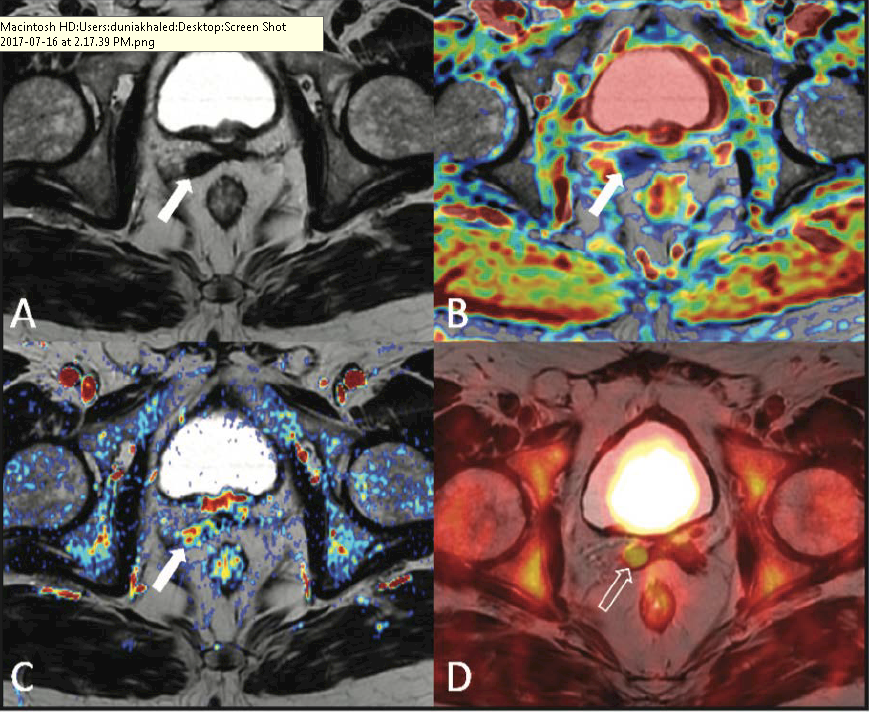

Introduction to Ureteroceles: Presentation, Diagnosis, and Initial Management

- Goals of ureterocele management include: prevention of renal damage, prevention of infection, and preservation of continence.

- Prenatal diagnosis of ureteroceles results in decreased morbidity both before and after surgical intervention.

- Patients presenting with obstruction and sepsis benefit from prompt, transurethral decompression.

- Any endoscopic technique chosen should aim to relieve obstruction while minimizing surgical morbidity and de novo reflux.